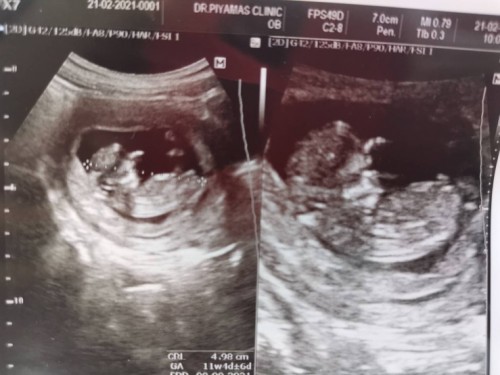

เจ้าตัวเล็ก 11w5d

เดือนหน้าคุณหมอบอกว่าจะรู้เพศน้องแล้วค่ะ ตื่นเต้นมากๆเลยค่ะ แอบลุ้นลูกสาว ปกติแม่ๆที่ได้ลูกสาวช่วงอายุครรภ์เท่านี้มีอาการอย่างไงบ้างค่ะ🥰🥰 ตอนซาวน์ดิ้นดุ้กดิ้กโชว์แขนขาใหญ่เลยค่ะ เพียงแต่ตอนนี้ตัวเล็กมาก แม่เลยไม่รู้สึก 😊